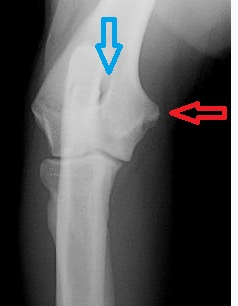

Blue arrow- supratrochlear foramen

Red arrow- medial epicondyle of the humerus